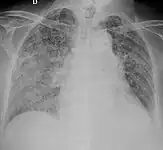

X-ray, showing bilateral interstitial infiltrates -

Miliary tuberculosis is a form of tuberculosis that is characterized by a wide dissemination into the human body and by the tiny size of the lesions (1–5 mm). Its name comes from a distinctive pattern seen on a chest radiograph of many tiny spots distributed throughout the lung fields with the appearance similar to millet seeds—thus the term "miliary" tuberculosis. Miliary TB may infect any number of organs, including the lungs, liver, and spleen.[5] Miliary tuberculosis is present in about 2 percent of all reported cases of tuberculosis and accounts for up to 20 percent of all extra-pulmonary tuberculosis cases.[6]

Testing for miliary tuberculosis is conducted in a similar manner as for other forms of tuberculosis, although a number of tests must be conducted on a patient to confirm diagnosis.[7] Tests include chest x-ray, sputum culture, bronchoscopy, biopsy, CT/MRI, blood cultures, fundoscopy, and electrocardiography.[1] The tuberculosis (TB) blood test, also called an Interferon Gamma Release Assay or IGRA, is a way to diagnose latent TB.A variety of neurological complications have been noted in miliary tuberculosis patients—tuberculous meningitis and cerebral tuberculomas being the most frequent. However, a majority of patients improve following antituberculous treatment. Rarely lymphangitic spread of lung cancer could mimic miliary pattern of tuberculosis on regular chest X-ray. [14][4]